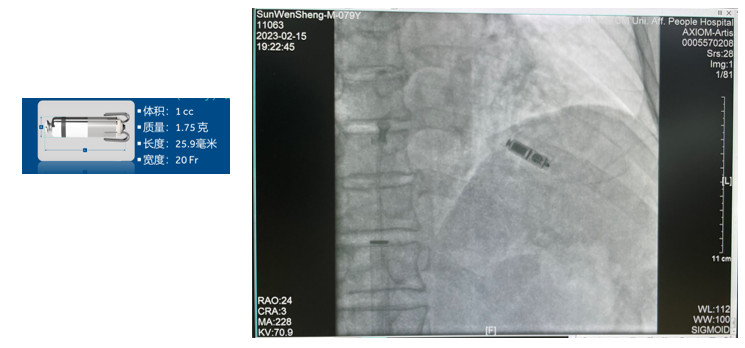

无导线起搏器植入术

植入式心电事件记录仪